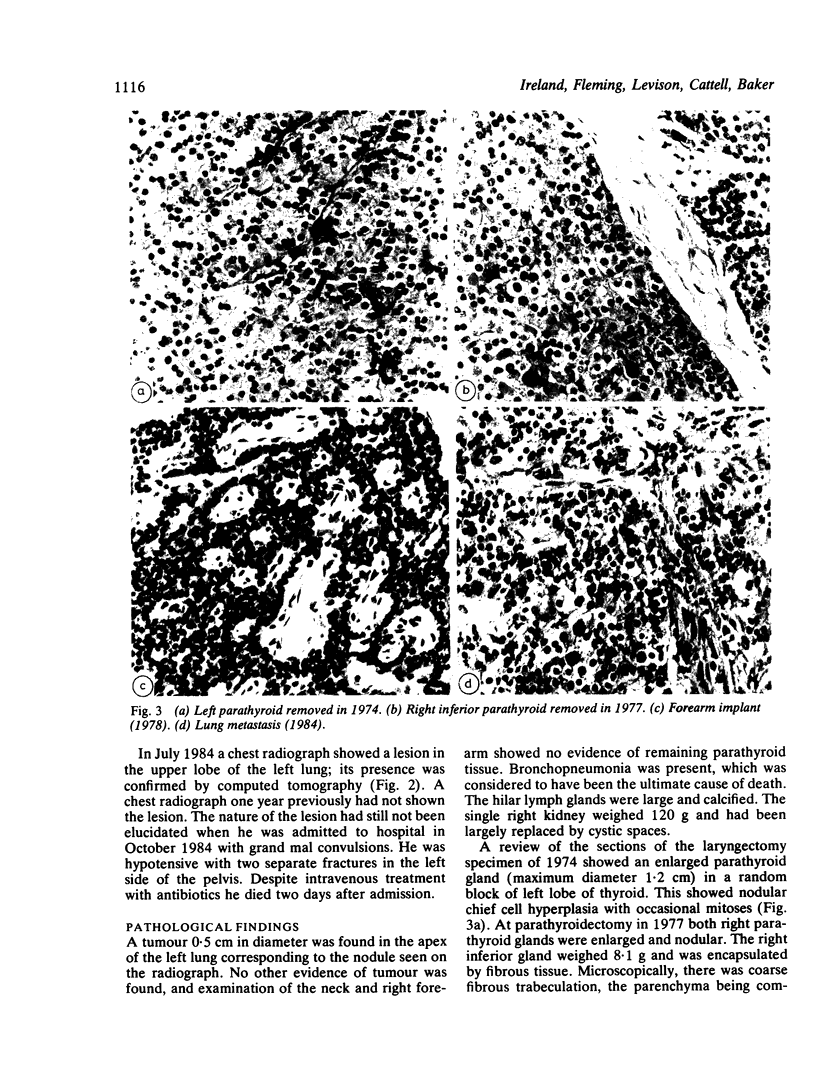

Carcinoma of the larynx was treated by irradiation followed by laryngectomy in a man who had been receiving regular haemodialysis for two years. At least one, and probably two, parathyroid glands were removed at this time, and the remaining two were removed three years later for tertiary hyperparathyroidism. A portion of one gland was implanted into the forearm. The forearm implant was resected the following year for recurrent hypercalcaemia. Six years later, again with recurrent hypercalcaemia, he died of bronchopneumonia. Metastatic parathyroid carcinoma was found in the apex of the left lung. The source of this parathyroid tissue and the possible role of irradiation in the pathogenesis of parathyroid cancer in this patient were investigated.